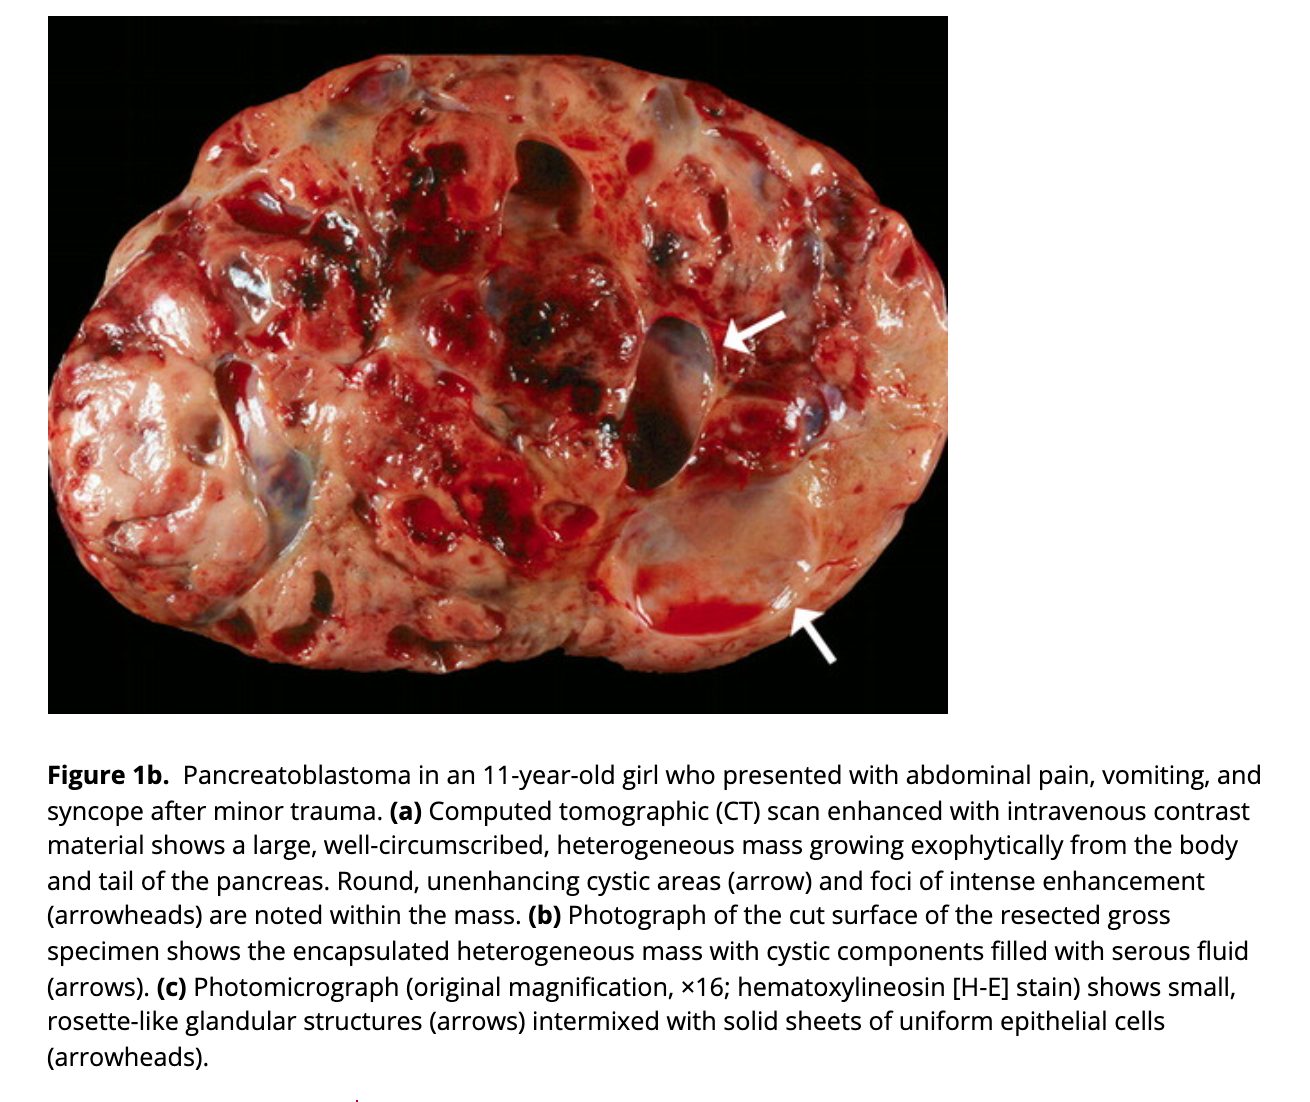

Pancreaticoblastoma

https://pubs.rsna.org/doi/10.1148/rg.264065012

Most common pancreatic tumour in children